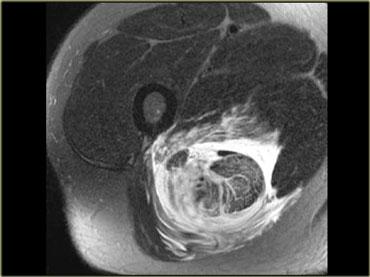

Hình bên trái là một ví dụ về bệnh cơ viêm.

Lưu ý tín hiệu tăng của tất cả các cơ ở tất cả các khoang.

Đây là hình ảnh phù nề.

Ngoài ra còn có phù nề ở tổ chức dưới da.

Rất hiếm khi chấn thương, chẳng hạn, lại biểu hiện phù nề ở tất cả các khoang.

Không có ổ tụ dịch bên trong cơ, nhưng cần lưu ý các ổ tụ dịch quanh mạc cơ.

Hình bên trái là một bệnh nhân viêm cơ.

Một lần nữa chúng ta thấy nhiều khoang bị tổn thương, phù nề lan rộng, tổn thương da và tụ dịch quanh mạc cơ.

Hình ảnh không đặc hiệu nhưng có thể gợi ý viêm cơ. Viêm cơ viêm thường có tính chất đối xứng hai bên.

Các đặc điểm MRI của viêm cơ bao gồm: cấu trúc bình thường trên chuỗi xung T1W, phù nề dạng lông vũ kèm ngấm thuốc, lưới hóa da và các bất thường KHÔNG giới hạn theo giải phẫu khoang hoặc thần kinh cụ thể.